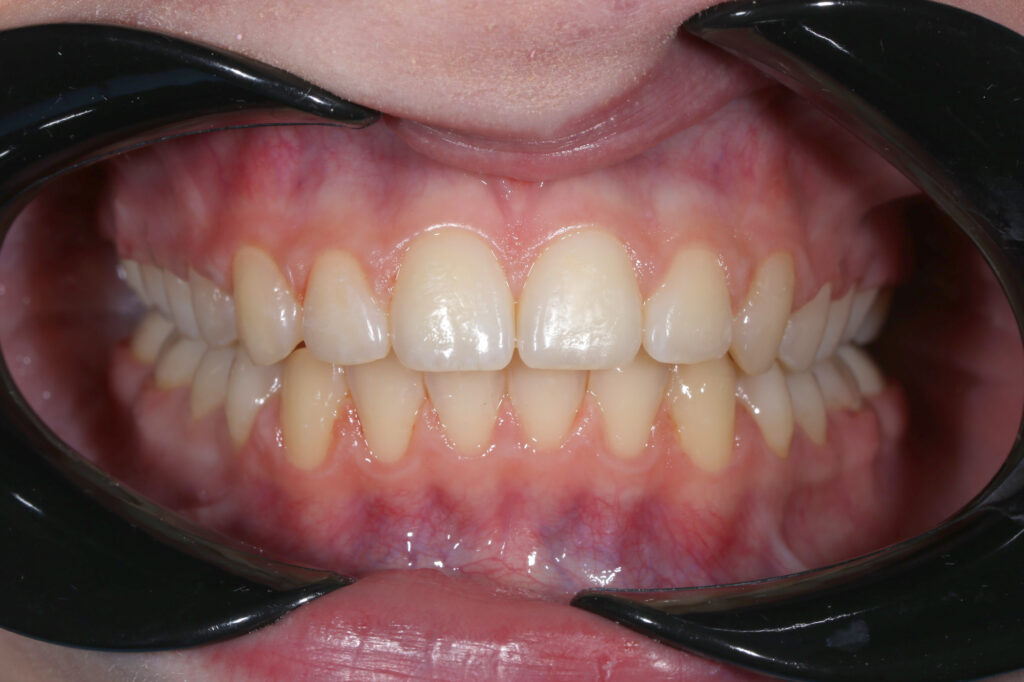

Результаты

результат лечения брекет-системой